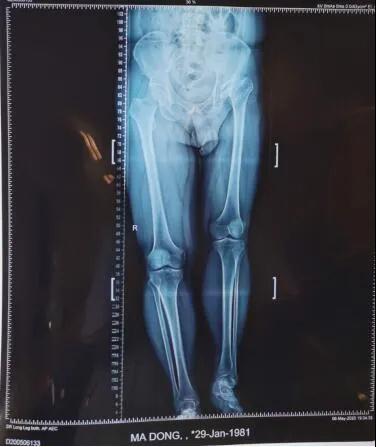

术后。

整个手术进行了两个小时,将置换后的髋关节假体准确复位,为患者重建了髋关节并且矫正两条腿基本恢复等长。

“人工关节置换手术的最大好处在于能够术后消除病变关节疼痛,大大改善关节功能,提高患者生活质量。” 李璐兵说,功能训练后,可以像正常人一样自如行走了。